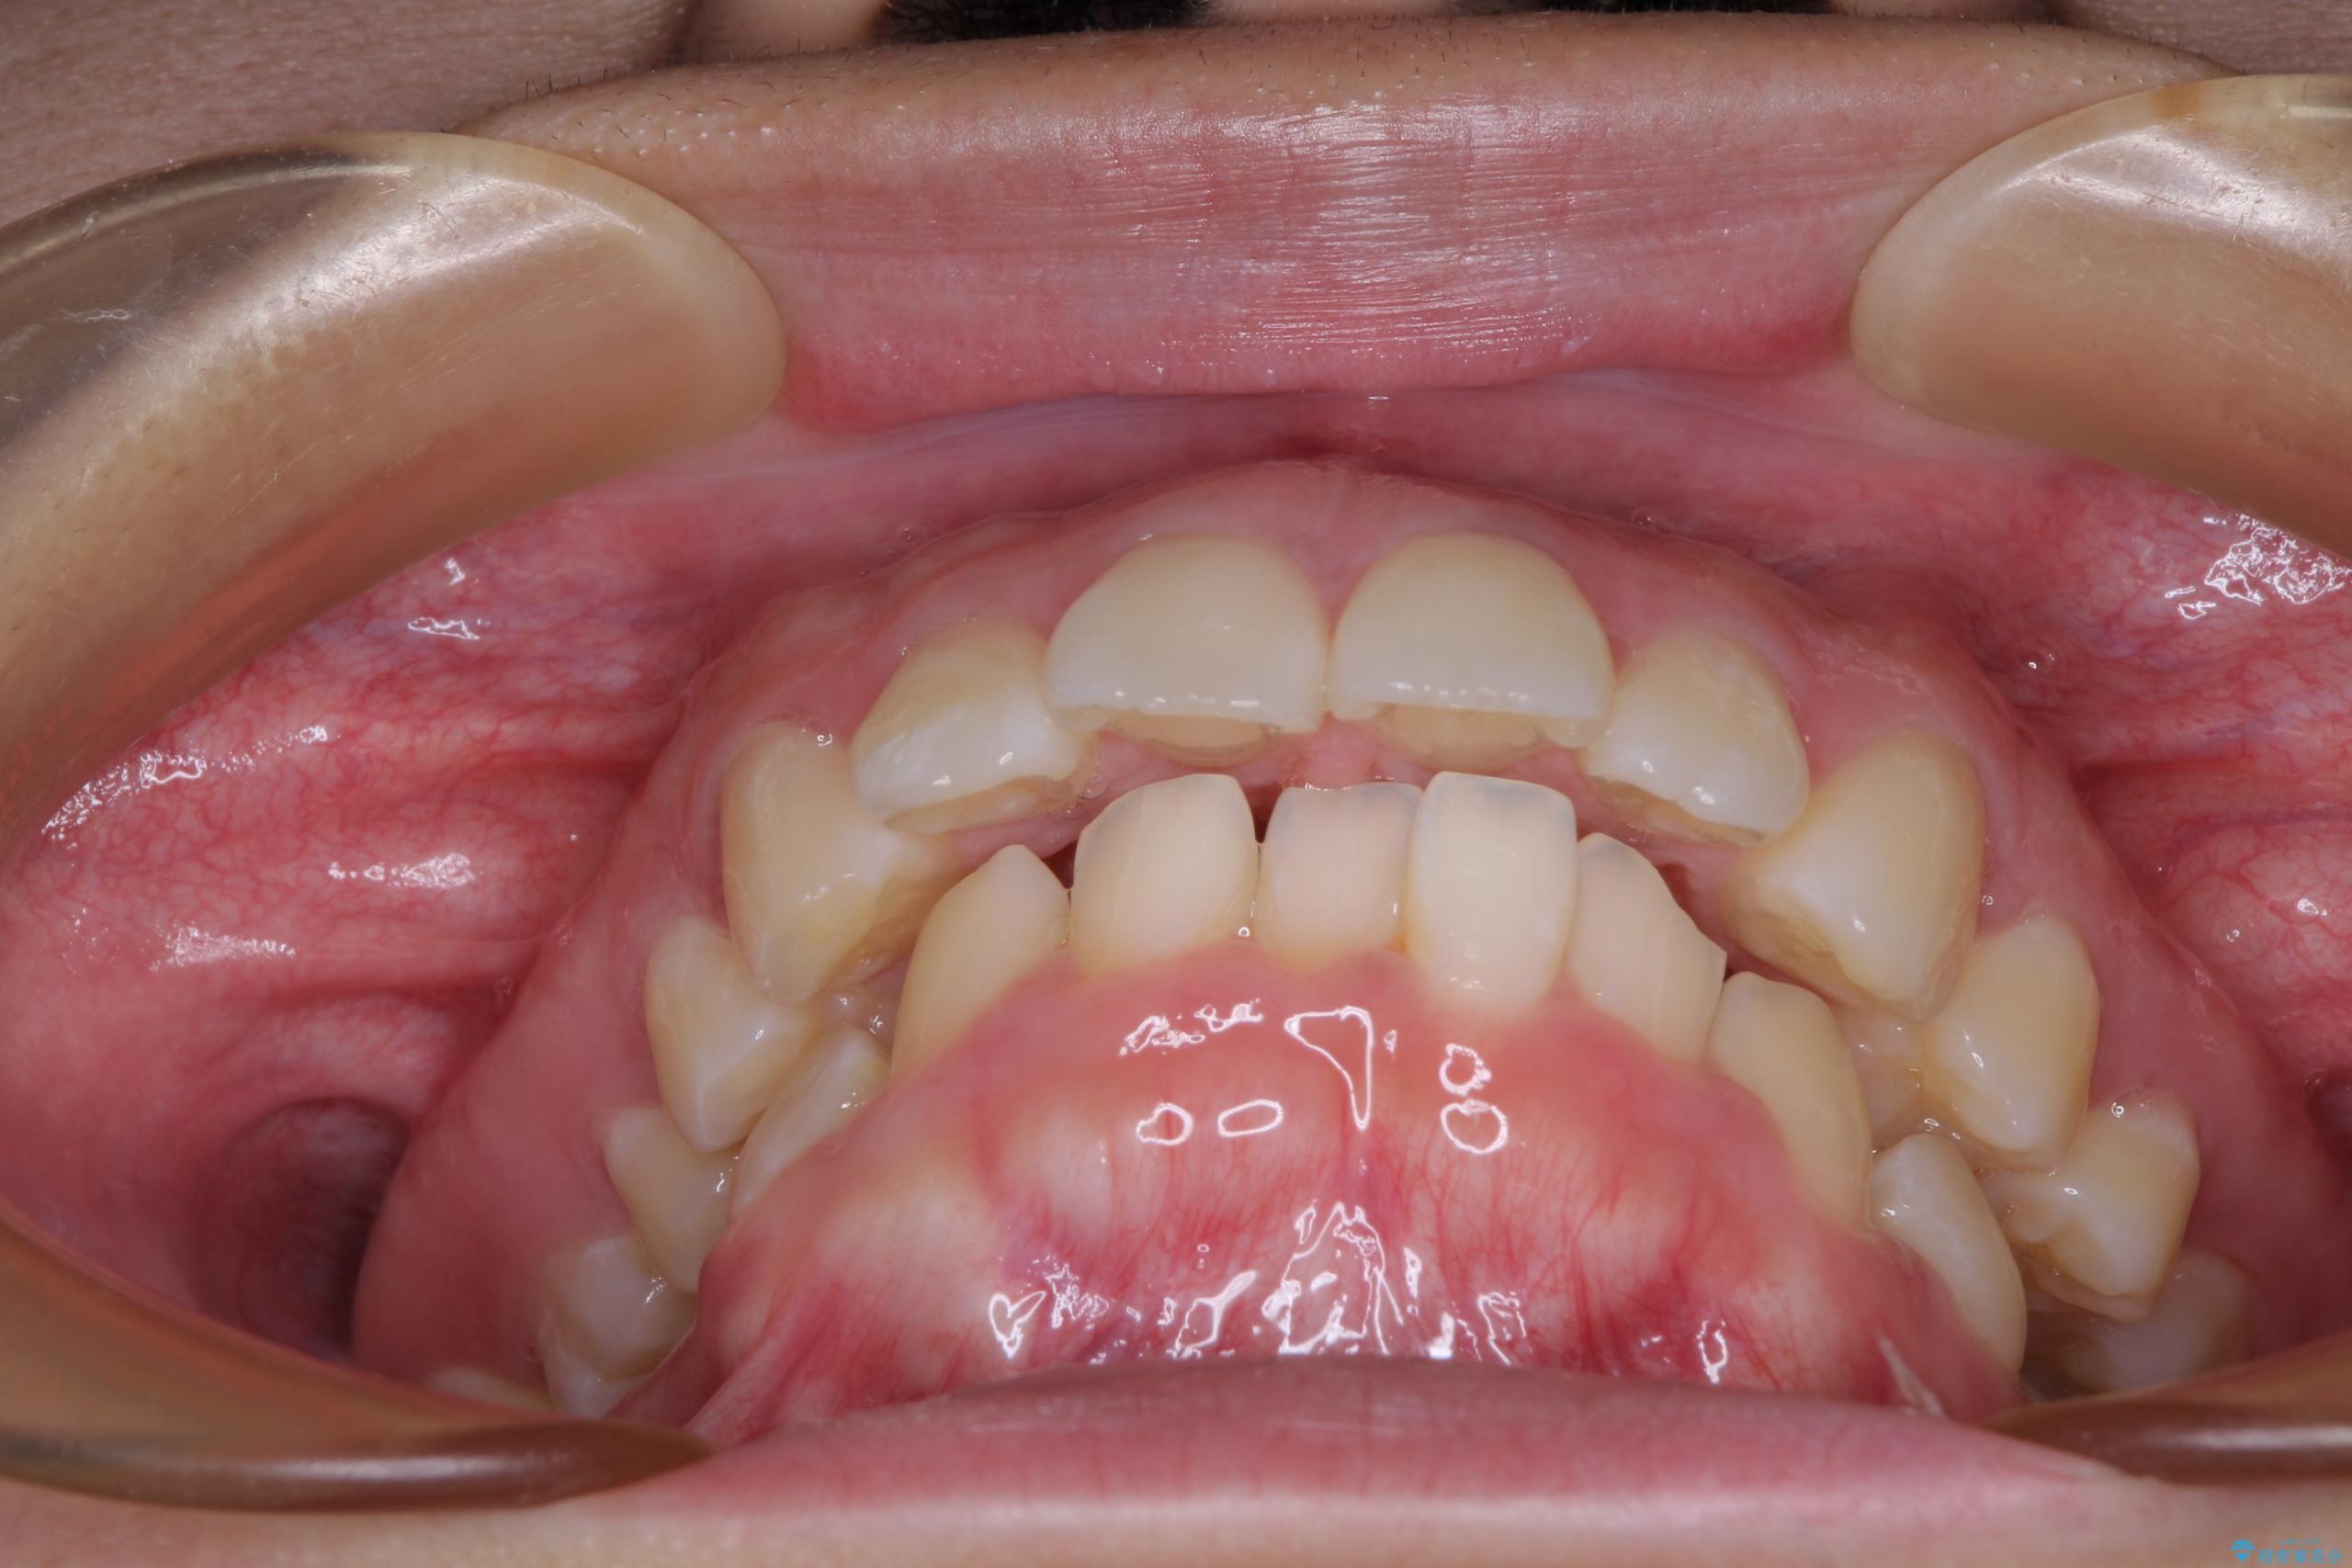

- 上顎前歯が飛び出していて唇がうまく閉じられないとのことで来院された患者様です。

くちばしのように前歯が突出していたため、口元を積極的に引っ込めるために、上下左右の小臼歯4本を抜歯することとしました。

また、上顎歯列が下顎に対して前方位に位置していたため、補助装置を用いて上顎歯列を後方に移動させ、より積極的に口元を下げるようにしました。

上下正中位置を改善するため、左下はイレギュラーに第二小臼歯を抜歯しました。そのため治療期間の長期化が予想されましたが、2年半ほどで期待通りの歯列に仕上げることができました。